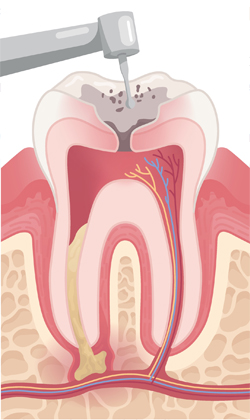

When a tooth is severely damaged or decayed, an infection can form and spread to the nerve tissue and pulp. To repair and save the tooth, a root canal treatment is performed by our endodontist. During the root canal procedure, the infected nerve and pulp are removed and the inside of the tooth is cleaned and sealed.

Infected pulp is removed. Root canals are cleaned out, enlarged, and shaped.